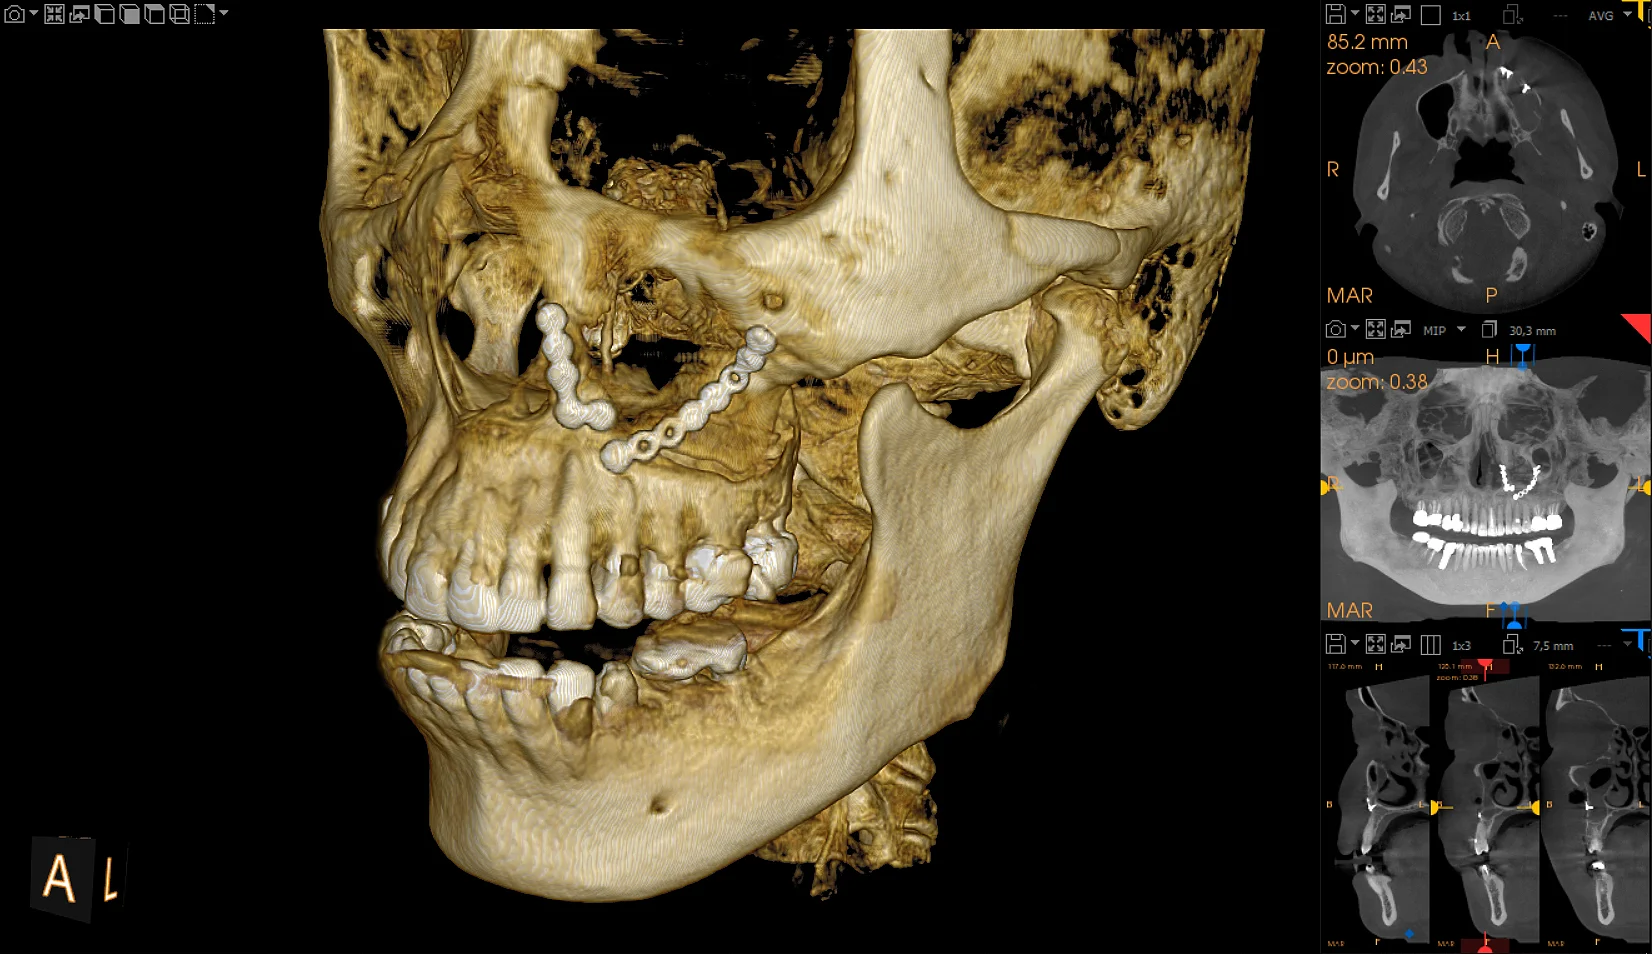

Skalabilni 5-u-1 skener dizajniran da raste s vašom ordinacijom

Pametne inovacije potiču preciznost na svakom pregledu

Pozicioniranje pokretano umjetnom inteligencijom pomaže u postizanju dosljednih rezultata bez napora

Kristalno jasne slike s ograničenim artefaktima i šumom

Najširi raspon veličina volumena s do 14 vidnih polja